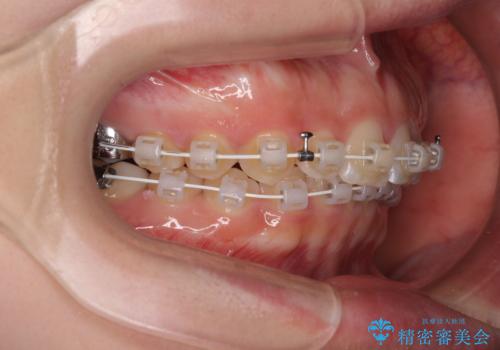

- 審美装置

- 1年3ヶ月

左上の歯列は補助装置により速やかに移動し、1年程度で奥歯の咬み合わせが改善され、1年3ヶ月の短期間でしっかりと仕上げることができました。